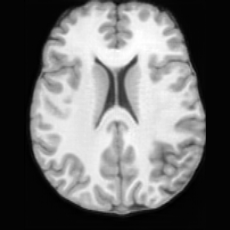

Conditional Generation. Fig. 4 (b) shows conditional generation results given a lesion mask. Conditioned on a single lesion mask, USB can generate an unlimited brain image samples that embed the specified lesion, producing diverse anatomical appearances while maintaining faithful pathological localization. As illustrated by the samples along each row, the generated pathological images exhibit variations in intensity, texture, and local tissue response.

In Tab. 1, we present the first quantitative benchmark evaluation of both generation tasks. For the unconditional generation task, we generated 256 paired lesion–brain samples for each lesion type (stroke and WMH). For the conditional generation task, we used masks from the ATLAS and ISLES test sets as stroke lesions, and masks from the ADNI test set as WMH lesions. Notably, for each lesion type, the unconditional generation achieved superior quantitative performance, highlighting that the paired diffusion mechanism effectively generates coherent lesion-brain pairs through joint modeling between USBbrain and USBlesion. Additional generation results are provided in Suppl. A.